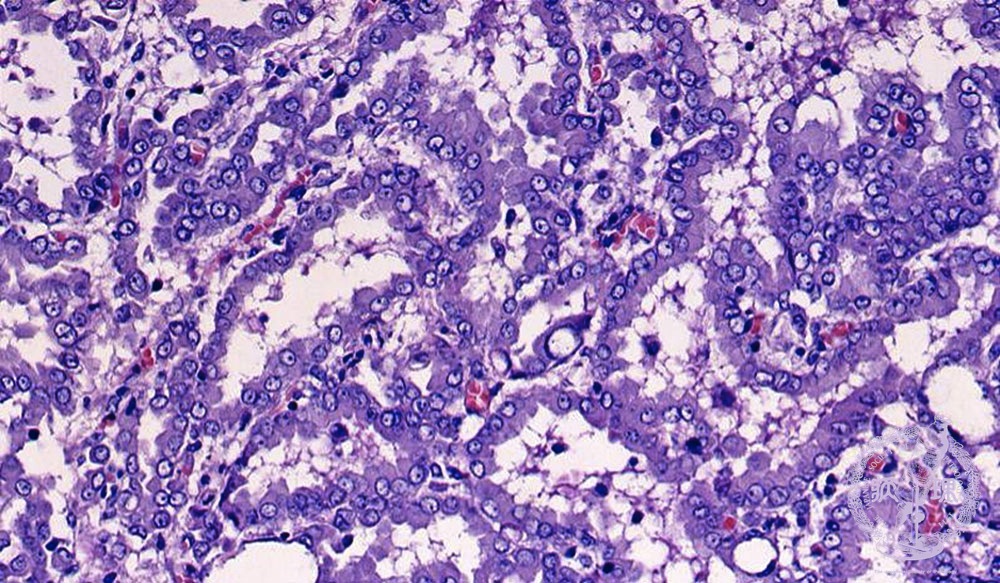

胸膜中皮腫ミクロ像(HE強拡大)

ミクロ像(HE強拡大):腫瘍細胞は腺管様構造、偽乳頭状構造を示しながら浸潤性増殖している。 HE染色のみでは肺腺癌との鑑別が困難なことがある。